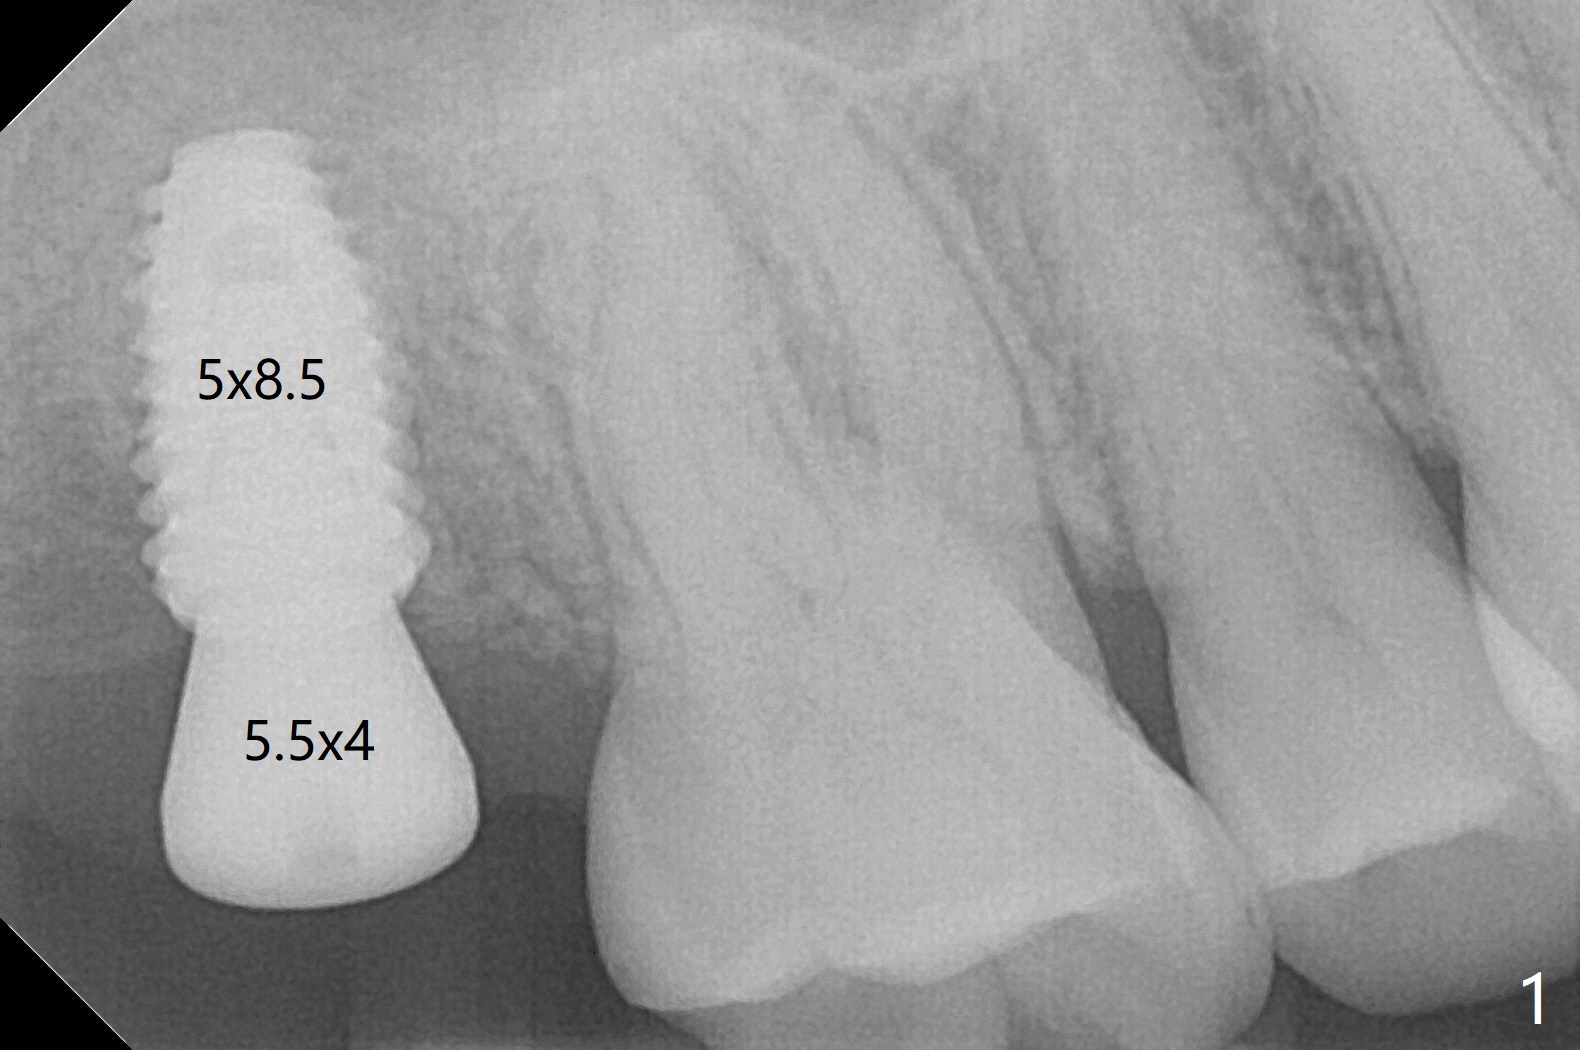

In spite of underprep (4.0x8.5 mm last drill), a 5x8.5 mm implant is placed at #2 with insertion torque ~ 15 Ncm (Fig.1). In addition to the large defect post implant removal with 4.5 month bone graft, he is a heavy gagger with limited mouth opening. Drill cylinders may not engage the metal sleeve precisely. A 5.5x4 mm healing abutment is placed with low emergency profile. The procedure, although difficult, finishes in a timely manner. Otherwise it would be a disaster for the patient and operator. PA taken 1 month postop shows slightly subcrestal placement (Fig.2). When a cemented abutment is placed 4 months postop, there is tenderness. In fact the implant is mobile. A 8x5 mm healing abutment is placed. Nine months postop, the implant remains slightly mobile (Fig.3); a healing screw is placed. The tooth #3 has sign and symptom of crack 13 months postop (Fig.4), related to root fracture of #19 (Fig.5, bruxism). In fact the tooth cracks nonsalvageable post RCT, 9 months post #2 healing screw, 21 months postop. Socket preservation will be carried out with sticky bone and PRF, while #2 implant will be uncovered, followed by placement of a short cemented abutment to hold periodontal dressing. Upper Molar Immediate Implant, Trajectory Xin Wei, DDS, PhD, MS 1st edition 11/27/2018, last revision 07/03/2021